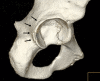

Methods: We reviewed the records of all 22 athletes presenting to our clinics with a posterior acetabular rim fracture confirming a posterior hip instability episode. Radiograph, CT, and MRI findings were documented in all patients. Intraoperative findings were recorded in patients undergoing surgery. There were 19 males and three females with an average age of 22 years (range, 13-31 years). Minimum followup was 2 years (average, 4 years; range, 2-16 years).

Results: The mean modified Harris hip score was 94, Hip Outcome Scores for Activities of Daily Living and Sport were 99 and 87, respectively, and 20 of 22 athletes returned to sport. The most common constellation of pathoanatomy was a posterior labral tear with rim fracture, anterior labral tear, capsular tear, ligamentum teres avulsion, and chondral injury of the femoral head with loose bodies. Sixteen of the 18 patients with femoroacetabular impingement (FAI) had a twisting or noncontact mechanism of injury.

Conclusions: When posterior hip subluxation is recognized and avascular necrosis avoided, these athletes generally have high functional outcome scores and high rates of return to sport. There is an apparent association between the occurrence of posterior hip instability and the presence of structural abnormalities often associated with FAI, which may contribute to a mechanism of FAI-induced posterior subluxation.